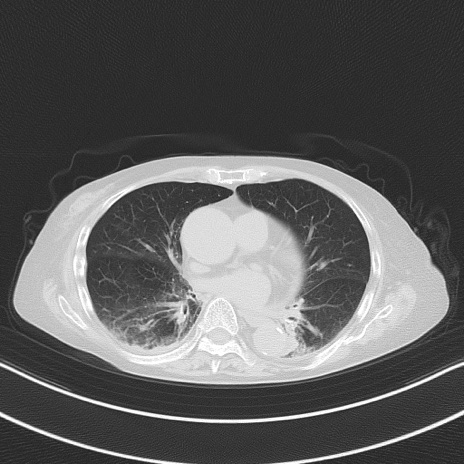

症例40(横断像)他院1日前

横断像

他院CT